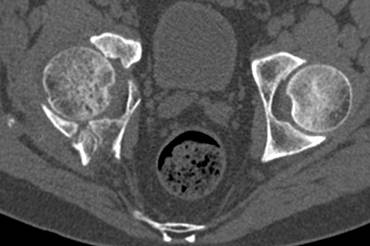

[Ortho] перелом правой половины таза

высылаю дополнительно  сканы.